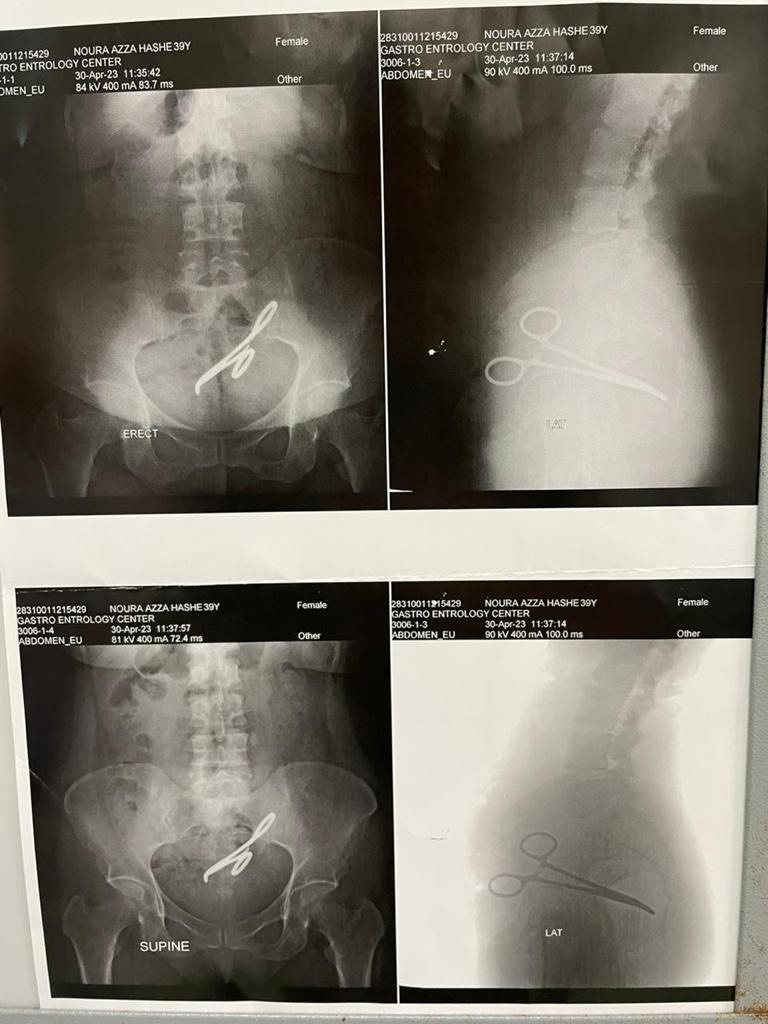

في واقعة فريدة من نوعها يتم اكتشاف آلة جراحية «جفت شرياني» بداخل تجويف البطن لسيدة أجريت لها عملة جراحية سنة 2017 «ولادة قيصرية» والسيد تبلغ من العمر 47 سنة، من محافظة الشرقية، كانت تعاني من آلام مبرحة بمنطقة الحوض منذ شهر مارس 2023 أعقبه حدوث ناسور شرخي مهبلي، مما حدا بها إلى الكشف عند عدد كبير من الاطباء.

وصرح الدكتور أمجد فؤاد رئيس اقسام الجراحة، بمركز جراحة الجهاز الهضمي بجامعة المنصورة، أن هذه السيدة حضرت فى العيادة الخارجية بالمركز وتم مناظرة الحالة ووجد أن بها شئ غريب وغير معتاد لذا أجرى لها على الفور الاشعات والمناظير والفحوصات اللازمه وعندها تم اكتشاف جسم معندي موجود بمنطقة الحوض لهذه السيدة.

وفي بداية هذا العام 2023 بدات هذه السيدة تعاني من آلام بالبطن والحوض وتكررت عليها هذه الآلام وازدادت حدتها وبدأ ظهور أعراض أخرى عبارة تعاني من وجود إفرازات شبيهة بالبراز بمنطقة المهبل لذا فقد أسرعت على الاستشارة الطبية المكثفة التي أثبت من خلالها وجود جسم معندي فى منطقه الحوض شبيه بآلة جراحية

وبعد التحضير المكثف والدقيق تم استكشاف الحالة فى مركز جراحة الجهاز الهضمى جامعة المنصورة، وجد خلالها آلة طبية جراحية بمنطقة الحوض عبارة عن جفت شرياني أصاب القولون والمستقيم والمثانة وعنهم الرحم بالالتهابات والالتصاقات الشديدة التي أسفرت عن حدوث ناسور بين المستقيم والمهبل

وفي جراحة صعبة ودقيقة ومعقد تم استخراج الجفت الشرياني وتم استئصال الأجزاء المصابة وذلك في خلال 5 ساعات كامله

تمت الجراحة بفريق طبي كبير ترأسها الدكتور أمجد فؤاد رئيس اقسام الجراحة و دكتور محمد عبد الرازق مدرس الجراحة، والطبيب محمد الكامل والطبيب محمد أمجد.